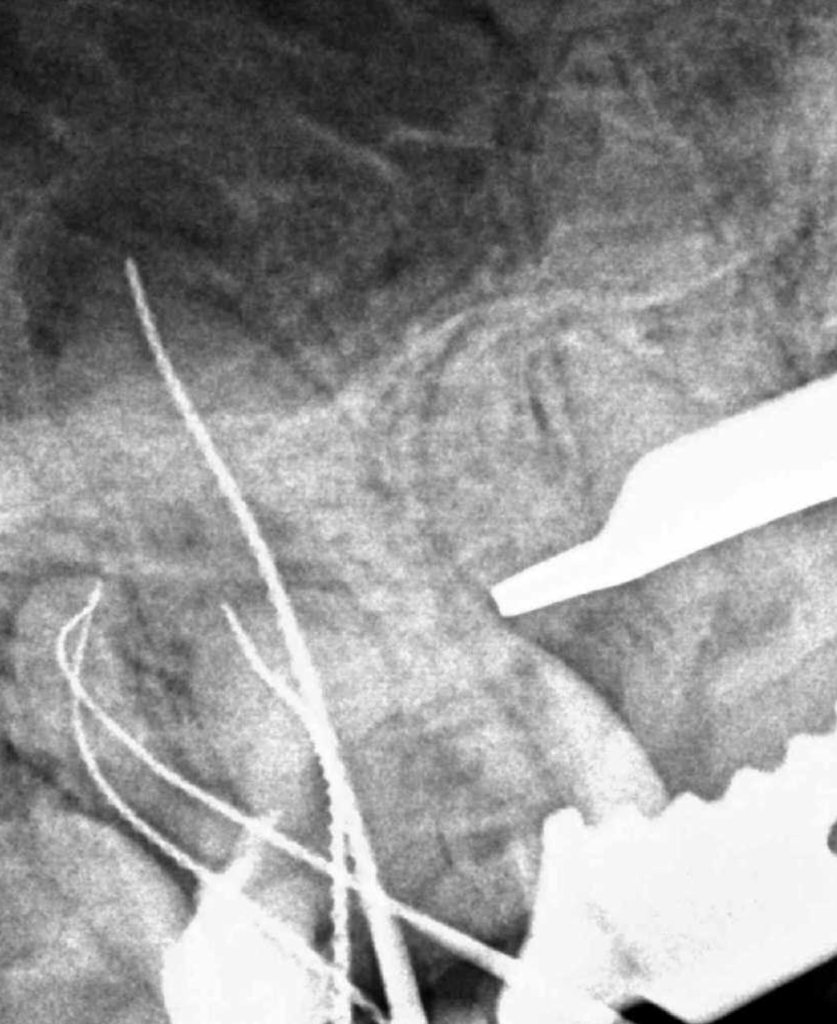

2 Limas rotas + reco Preendo

Lima en conducto MV

Lima rota apical curación un año

Retratamiento Lima Rota Apical